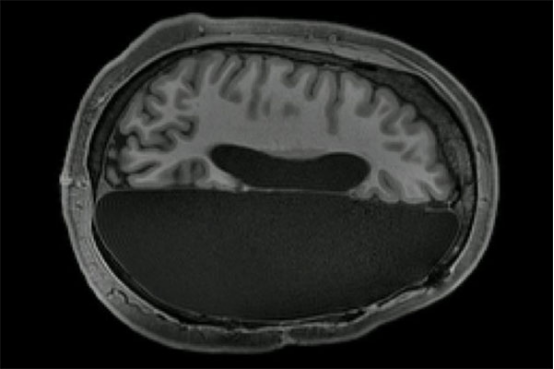

实际上 , 脑机接口就是通过在头骨开口并且植入电子芯片来进行工作的 , 借助于人类此前积累的大量经验 , 科学家会通过电子芯片发射正确的脑电波 , 从而控制人体的活动 , 即便只有一小部分能够合理应用 , 也是一个巨大的进步 。